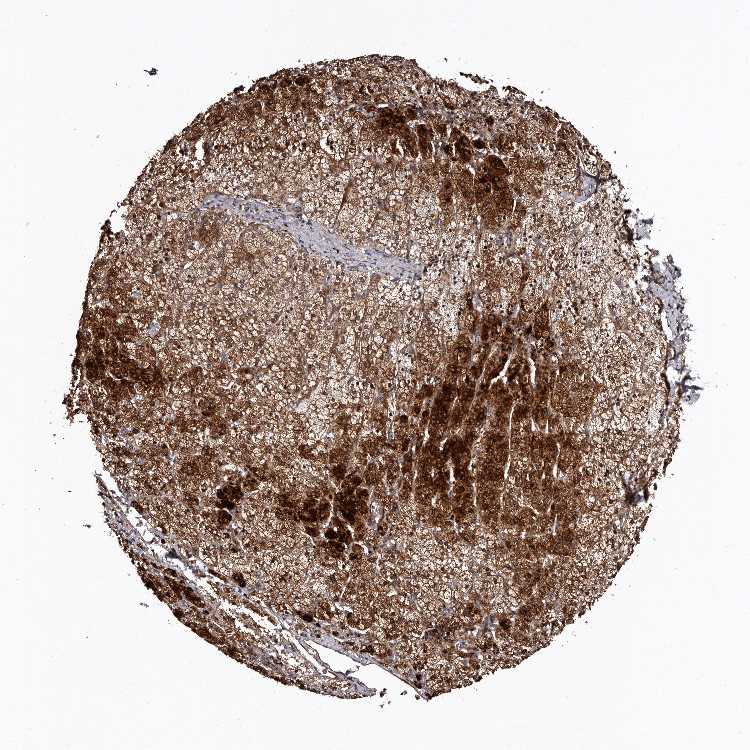

ADRENAL GLAND - Antibody stainingi

Antibody staining in the annotated cell types in the current human tissue is reported as not detected, low, medium, or high, based on conventional immunohistochemistry profiling in selected tissues. This score is based on the combination of the staining intensity and fraction of stained cells.

Each image is clickable and will lead to virtual microscopy that enables deeper exploration of all samples and also displays staining intensity scores, fraction scores and subcellular localization as well as patient and tissue information for each sample.

Antibody HPA029529

Glandular cells High